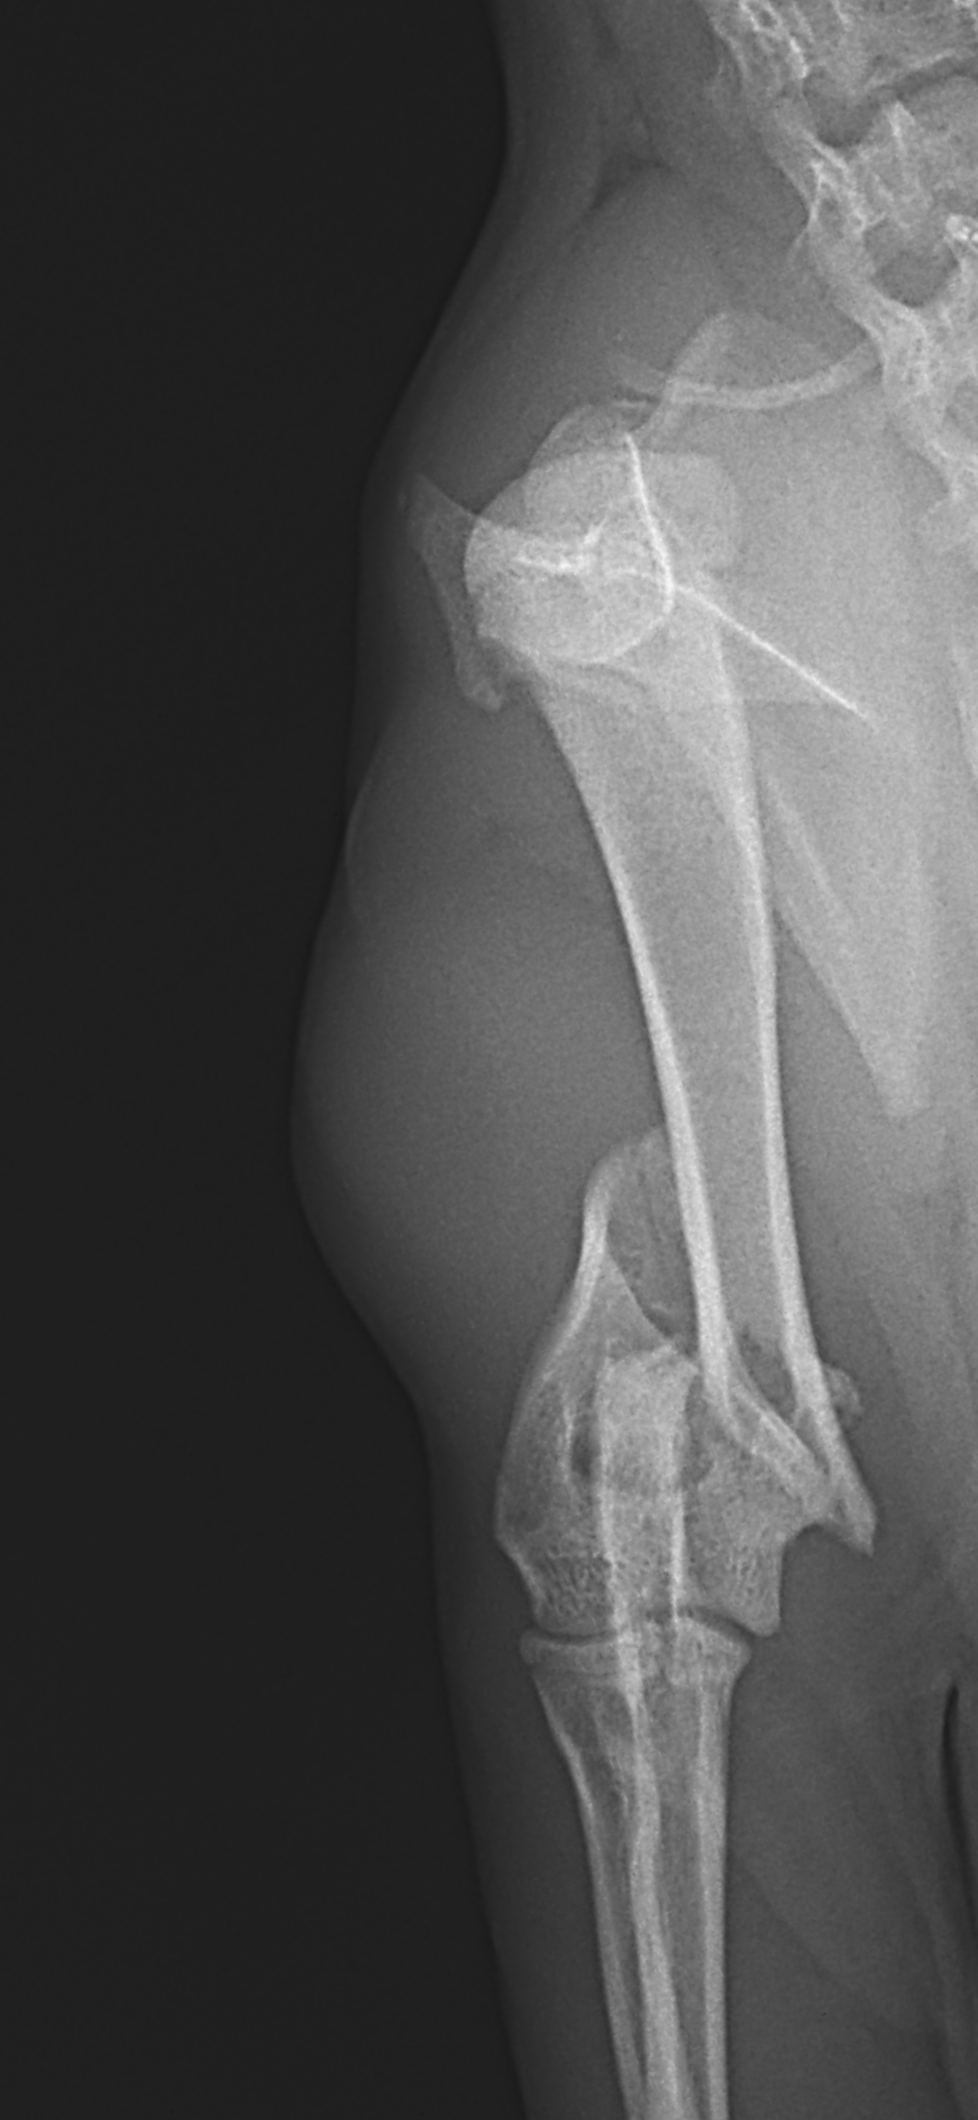

上腕骨遠位粉砕骨折

若い猫ちゃんが部屋で遊んでいたところ、不運にも上腕骨を粉砕骨折してしまったとのこと。かかりつけ医から固定術の依頼がありました。粉砕部分をOrthogonal Plateで固定術を行いました。